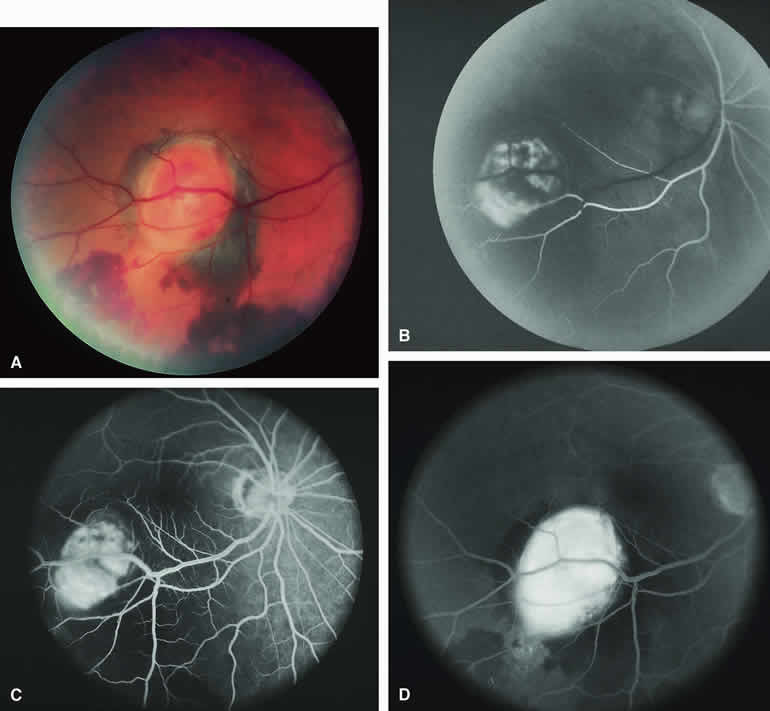

Amelanotic Choroidal Nevus

Approximately 10% to 15% of choroidal nevi are largely or completely amelanotic clinically. Fluorescein and ICG angiography of an amelanotic choroidal nevus (see Fig. 3) tend to show less prominent hypofluorescence of the lesion than they do with darkly melanotic nevi. Because of the lack of intracellular melanin pigment within the nevus cells, some large-caliber choroidal blood vessels running through the nevus may be visible in the region of the mass (see Fig. 3B and C). These choroidal blood vessels are better defined by ICG angiography than by fluorescein angiography. Amelanotic choroidal nevi often appear mildly hyperfluorescent in late-phase frames (see Fig. 3D).